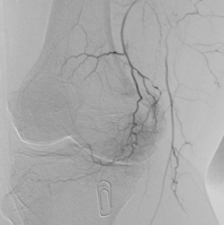

Kniegelenkembolisation

Dabei werden gezielt kleine Blutgefäße, die zur Entzündung und zum Knieschmerz beitragen, durch winzige Partikel verschlossen. Der Eingriff erfolgt schonend über einen kleinen Zugang in der Leiste, meist unter örtlicher Betäubung. Die meisten Patienten spüren bereits kurz nach dem Eingriff eine deutliche Schmerzlinderung und können rasch in ihren Alltag zurückkehren.

Die Kniegelenkembolisation stellt keinen Ersatz für eine Knieprothese dar, sondern dient lediglich der Schmerzbehandlung und kann eine Operation hinauszögern.